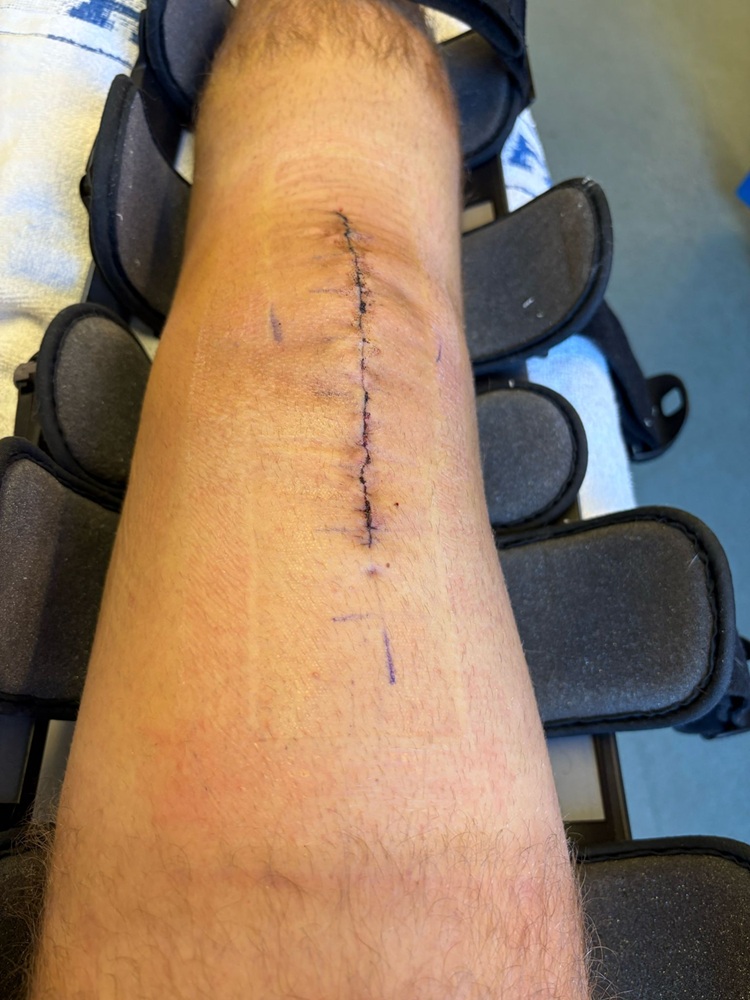

So this is after his operation, I’ve spared you all the x-ray showing the wire cage wound around his kneecap pulling the pieces together. His friends think his scar is cool. He has a leg brace which prevents bending of the leg for now. This is released slowly over time. Physio has started but recovery is likely to be 12 months minimum. Pain has eased somewhat, although he has returned to school on crutches after Easter and it is getting painful again, as the movement and use of it increases. He is also very tired which won’t help the revision needed for his GSCE exams in a month. Worrying times.